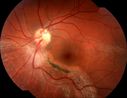

Eccentric Disciform Scar - Breakthrough Vitreous Hemorrhage - InferoTemporal Subretinal Fibrosis - Ectopic Choroidal Neovascular Membranes931 views88-year-old man has noticed for the last few months the vision in the right eye is foggy, like there is a film in the eye or a haze, His vision is 20/16 in each eye.

Right eye - inferotemporal periphery there is a hemorrhage at the equator at about 7:00 o’clock, which is about 4-disc diameters across and adjacent to that there is scarring.

Left eye - large disciform scar inferotemporally